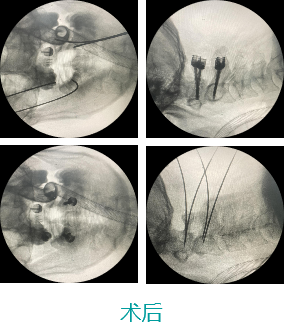

天玑II 辅助颈椎椎弓根螺钉内牢靠术

基本情形:患者男,,,,,49岁,,,,,枢椎骨折

病例泉源:北京积水潭医院